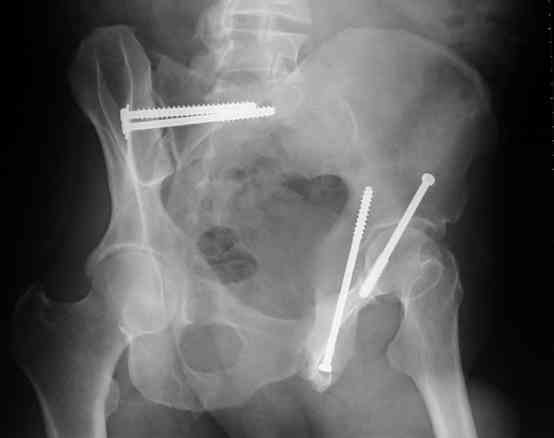

Routine Fixation

AC Screw

PC Neutr Plate

Others

The unstable caudal segment is secured by the lower 2 plate screws and the AC medullary screw... always assure that your fixation is sufficient to defeat the instability... part of your prop plan... but assure it before you close... it¹s your last chance... you shouldn't have to be pushing on the hip in contorted ways to determine your fixation stability...you can if that makes you 'comfortable'.